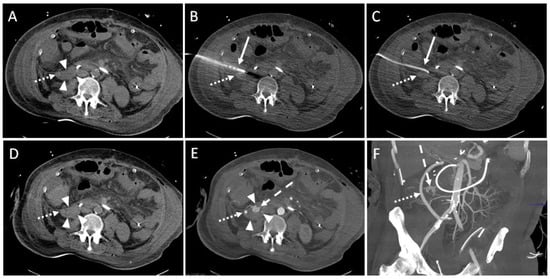

Figure 4. Example of a CT-guided drainage placement with significant complications following SIR guidelines. A 47-year-old male with history of liver transplantation due to alcoholic cirrhosis. After six weeks, an increase in inflammatory parameters was observed. (A) CT planning scan 52 days after transplantation: a fluid collection (arrowheads; density: 6 Hounsfield units (HU)) encompassing the bypass (dotted arrow) between right common iliac artery and hepatic artery in the right paracolic gutter. (B) Using lateral access via the retrocolic space, a 10F pigtail drainage (solid arrow) is placed under CT fluoroscopy. Dotted arrow: drainage trajectory anterior to the bypass. (C) After removal of the Trocar, a correct position of the drain (solid arrow) was shown. Several milliliters of serous fluid could be aspirated. Dotted arrow: bypass. (D) An unenhanced CT control scan revealed increased density (30 HU; compare to figure (A)) of the fluid collection (arrowheads) in the right paracolic gutter suspicious of acute bleeding. Dotted arrow: bypass. (E) Enhanced follow up CT scan 10 min after drain placement shows contrast agent extravasation (dashed arrow) originating from a branch of the right colic artery. Due to the arterial contrasting, the bypass (dotted arrow) is now clearly delineated. Arrowheads: fluid collection. (F) Coronary maximum-intensity projection (40 mm) showed an intact, inconspicuous bypass (dotted arrow). Dashed arrow: contrast agent extravasation. The injured vessel was subject to successful immediate revision surgery.